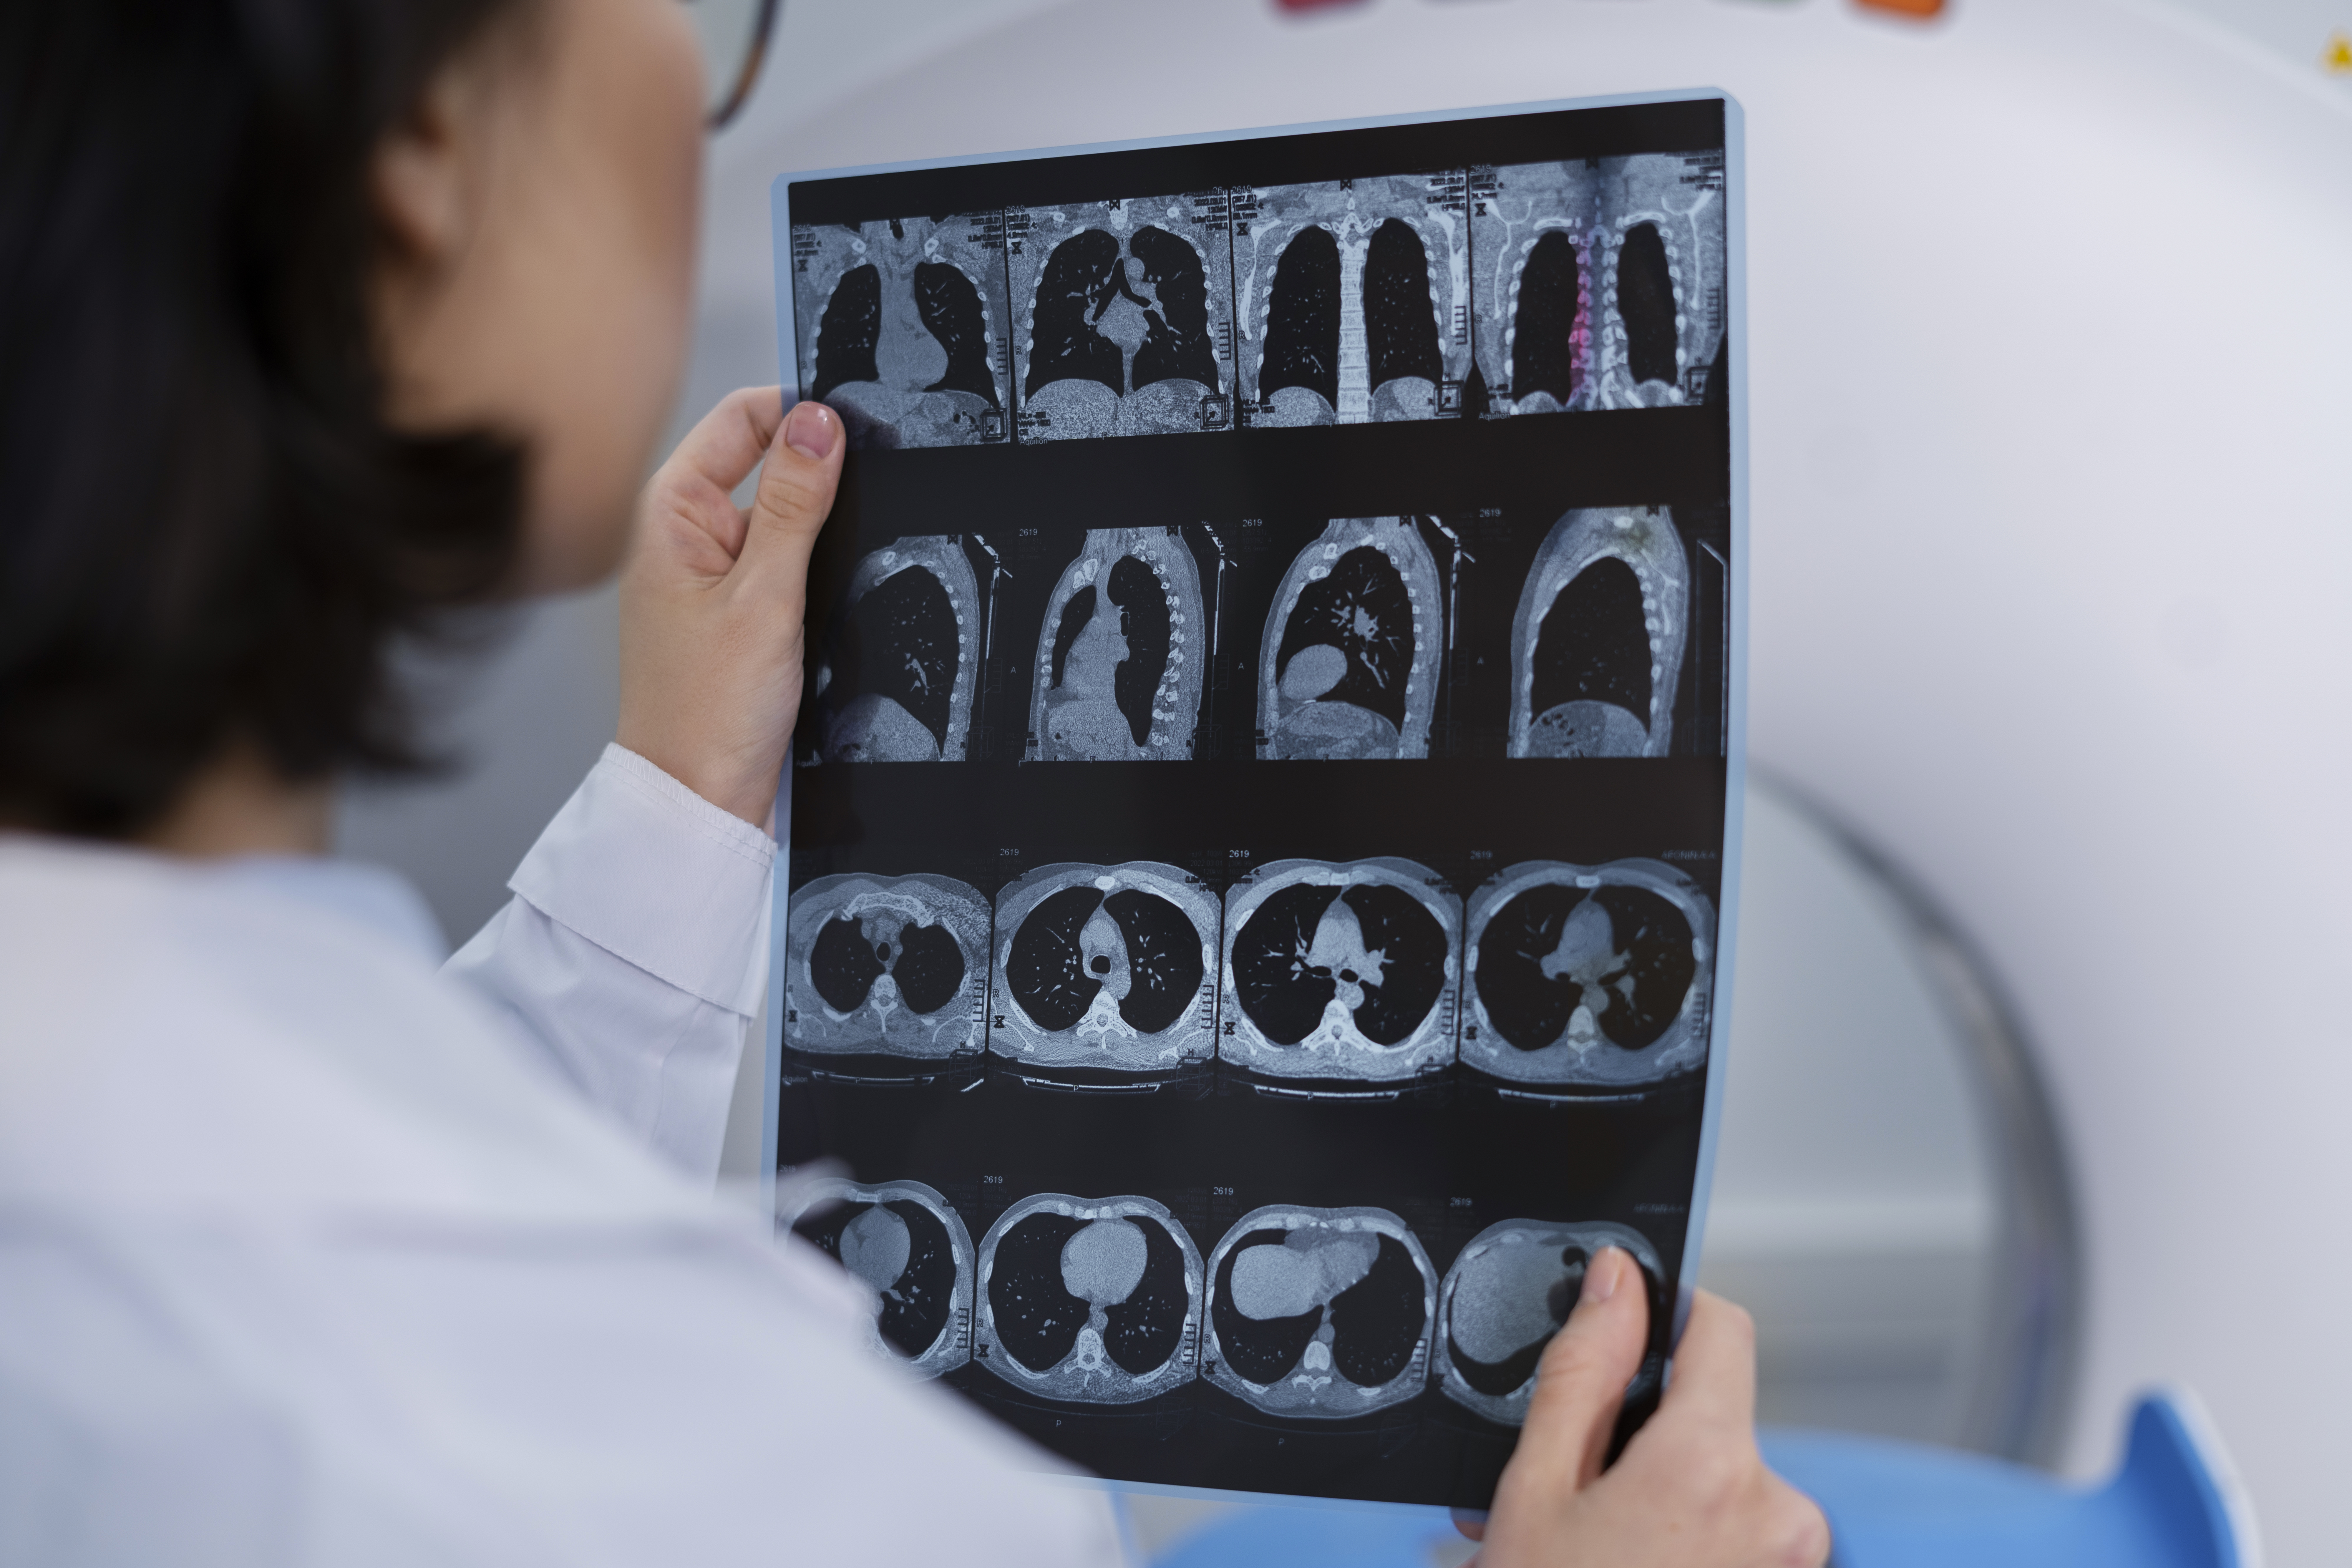

Radiologia DIGITAL RX

A radiologia DIGITAL o "RX" é muito utilizado em diagnósticos rápidos e precisos, de fácil acesso é ideal para as patologias como traumas e lesões em órgãos como o pulmão, coração e rins.